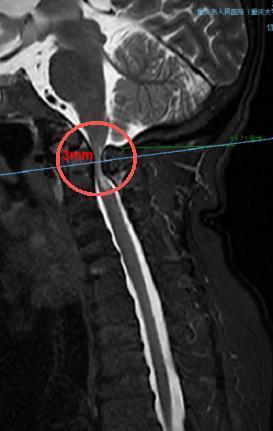

术前,颈椎MRI显示,患者脊髓严重受压(圆圈处)。重庆市人民医院(重庆大学附属人民医院)供图